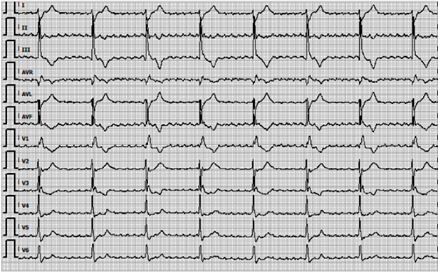

In April 2023, a 70-year-old male presented to the outpatient clinic of gastroenterology with complaints of dysphagia and weight loss. A diagnosis of iT3N1M0 adenocarcinoma of the distal esophagus was established. Prior to a planned curative esophagectomy, chemoradiotherapy was administered according to the regimen used in the CROSS-trial (1). In November 2023, following an R0 resection with residual pathological disease, the patient began adjuvant immunotherapy with nivolumab (2). Fourteen days after starting nivolumab, the patient developed complaints of palpitations and worsening dysphagia. Liver enzyme abnormalities were noted (ALAT 186 U/L, ASAT 263 U/L, LD 508 U/L) as well as thyroid dysfunction (TSH 0.001, FT4 51 pmol/L, FT3 17 pmol/L), with no signs of abnormalities in other endocrine axes. Hepatitis B/C/E serology and EBV/CMV IgM were negative, and abdominal ultrasound revealed no liver abnormalities. A suspicion of immune-related hepatitis, gastritis, and thyroiditis was raised. The patient was admitted to the hospital, and intravenous prednisone (80 mg) and propranolol (40 mg) were initiated. Two days later, liver enzymes showed insufficient improvement (Y-GT 83 U/L, ALAT 451 U/L, ASAT 196 U/L, LD 700 U/L), prompting the initiation of intravenous methylprednisolone (100 mg), which was increased to 200 mg after 2 days due to continued inadequate response. Six days later, the patient developed bradycardia (47 bpm) and required supplemental oxygen. An ECG revealed a complete AV-block with atrial flutter (Figure 1), along with elevated troponin (2729 ng/L) and CK levels (1090 U/L). Although MRI of the heart showed no significant abnormalities, immune-related myocarditis was considered. Mycophenolate mofetil (MMF) twice a day 1000 mg was started, and methylprednisolone was continued. Subsequently, the liver function improved. Due to persistent complete AV-block, a pacemaker was implanted.

Figure 1: ECG with an atrium flutter and total AV-block provoked by inflammation in myocarditis.